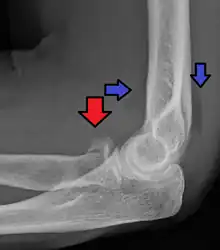

| Radial head fracture (red arrow) with posterior and anterior sail sign (blue arrows) | |

Radial head fractures are diagnosed from a clinical assessment and diagnostic imaging. Clinical assessment may include pain or tenderness at the radial head, bruising, swelling, and a limited range of motion of the injured elbow.[2] Diagnostic imaging may include ultrasound, plain radiography (x-ray imaging), Computed tomography scan (CT), and magnetic resonance imaging (MRI).[2][4] A fat pad sign may be present on diagnostic imaging and may indicate a radial head fracture.[5]